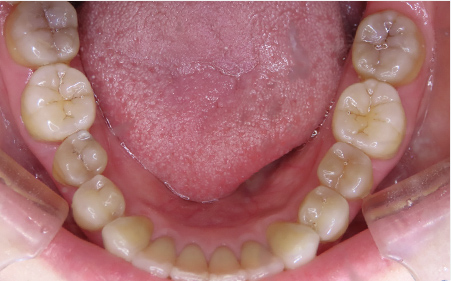

CASE08

Before

After

| 施術名 |

インビザラインコンプリヘンシブを用いた矯正治療(叢生) |

| 治療期間 |

1年 |

| 治療費 |

880,000円(税込) |

| リスク |

マウスピース装置により疼痛・咬合時痛を生じる事があります。割れたり壊れたりする事があります。 |

歯科医師からのコメント

「上顎八重歯が気になる」で来院されました。分析すると、軽度なねじれでしたのでインビザラインGoにて治療をすすめていきました。マウスピースを積極的に使用し、順調に治療がすすんでいきました。仕上がりにとても満足しておられました。